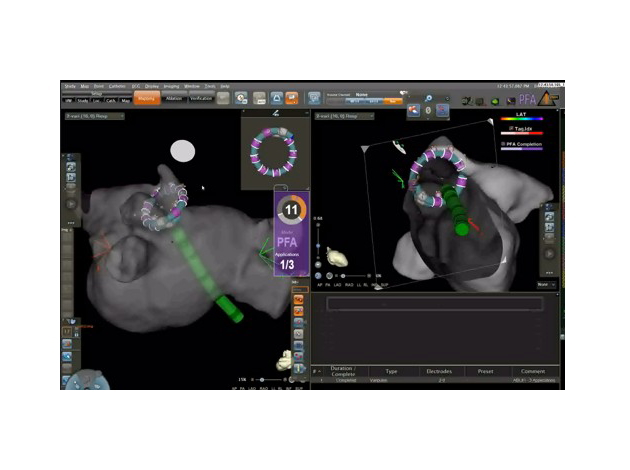

当グループでは、アブレーション治療における質と安全性を最優先としつつ、積極的に新技術を取り入れています。全症例の約7割を占める心房細動に対しては、CARTOおよびEnSite NavXなどの3Dマッピングシステムを駆使し、高周波アブレーション、クライオバルーン、レーザー、ホットバルーンといった多様なエネルギーデバイスを適切に選択しています。特に持続性心房細動に対しては、左房基質に対する周波数解析、エクストラマッピング(ExTRa Mapping)によるローターの同定、CARTO FINDERによるトリガーの同定などに基づき、患者ごとに最適化された戦略的アプローチを行っています。さらに、マーシャル静脈という細い血管にエタノールを注入するケミカルアブレーションを行い、難治性心房細動の治療成績向上につなげてます。また、近年導入されたパルスフィールドアブレーション(PFA)は、周囲組織への影響を最小限に抑えつつ心筋細胞を選択的に電気的不可逆変性に導く次世代エネルギー源として注目されており、当科でも積極的な導入と技術検証を進めています。

VARIPULSE

PULSE SELCT

QDOT MICROカテーテル